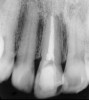

Figure 1a  Panoramic (A) and periapical radiographs (B, C) reveal the absence of periapical rarefaction in the area of the upper right central incisor. However, evidence of apical periodontitis can be seen clearly using the CBCT21 (D, E).

Figure 1a

Figure 1b  Panoramic (A) and periapical radiographs (B, C) reveal the absence of periapical rarefaction in the area of the upper right central incisor. However, evidence of apical periodontitis can be seen clearly using the CBCT21 (D, E).

Figure 1b

Figure 1c  Panoramic (A) and periapical radiographs (B, C) reveal the absence of periapical rarefaction in the area of the upper right central incisor. However, evidence of apical periodontitis can be seen clearly using the CBCT21 (D, E).

Figure 1c

In addition to linear accuracy, it has been suggested that CBCT can have diagnostic accuracy with regards to periapical lesions.17-19 In one of these studies,17 periapical lesions were analyzed with CBCT, then surgically excised and biopsied to compare with histology. The authors found comparable results. Although the study showed promising results with CBCT, the researchers conceded that histology remains the gold standard in the diagnostic armamentarium. In another study,19 the ability to identify periapical lesions was assessed using radiographs and spiral CT. With CT, 100% of lesions were identified, while only 78% were identified with radiographs alone. Concomitantly, the location of the lesions proximal to the inferior alveolar nerve was visualized more readily with CT (100% vs 39%). Figure 1A through Figure 1E illustrate a case in which an endodontically treated tooth appeared normal on panoramic and periapical radiographs. Only CBCT showed the presence of apical pathology.6

Initially, case studies appeared in the endodontic literature in which patients underwent CBCT imaging for the purposes of diagnosis20-22 and presurgical treatment planning.19 Recent reports have successfully shown the use of CBCT to locate missed canals,23 detect the extent of dentoalveolar fractures,20 identify resorption patterns,22 and compare cystic with granulomatous periapical lesions.17 Figure 2A through Figure 2C show a case in which the missed canal was suggested by periapical radiographs but confirmed with CBCT.24 Similarly in Figure 3A through Figure 3D, the additional diagnostic information attained from CBCT confirmed the diagnosis and extent of the root fracture, which initially was observed in the periapical radiographs (Figure 4A and Figure 4B).20 Notably, the extent of the lingual fracture as well as any alveolar complications could be visualized by CBCT only.